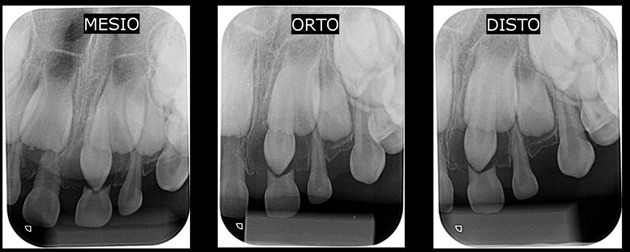

RADIOGRAFIA PERIAPICAL

TÉCNICA DE CLARK